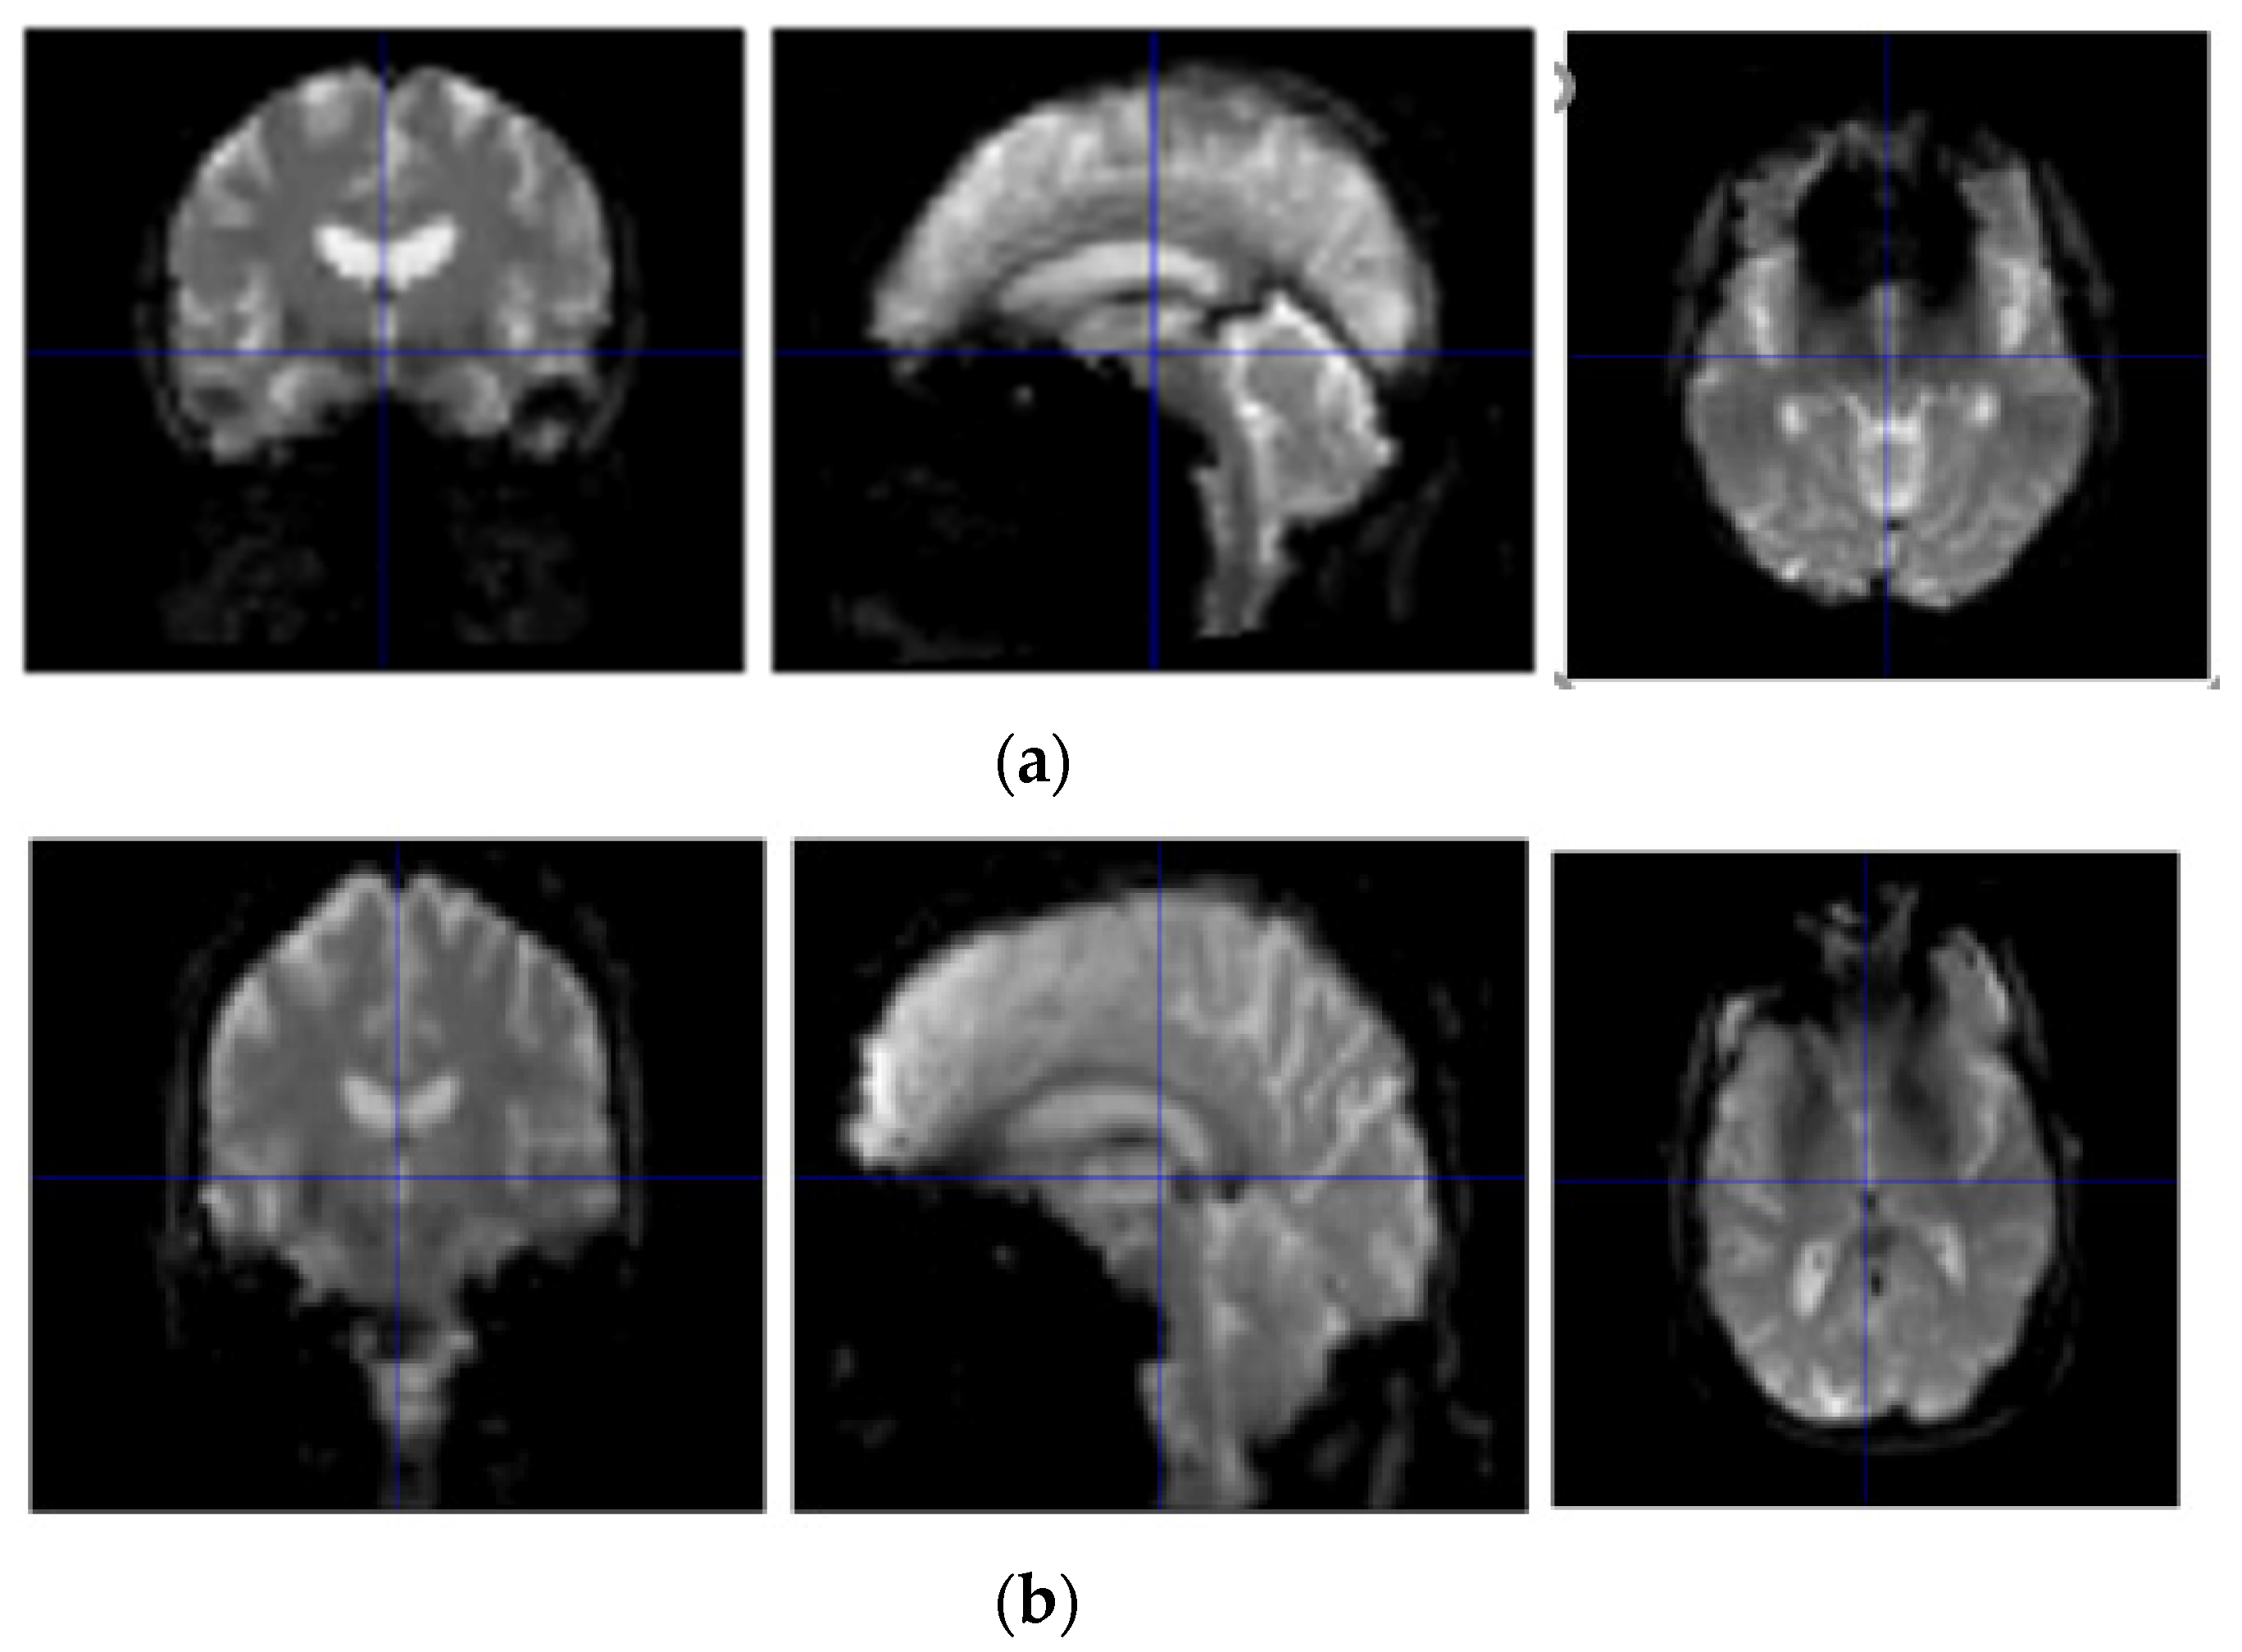

As can be seen from Table 1, with the aggravation of the disease, MMSE scores showed a downward trend, while CDR showed an upward trend. A statistical analysis of basic information was obtained by SPSS software [17]. Sample scanners selected from the ADNI are from Philips Medical Systems. The resting state fMRI scan sequence (EPI) has a total of 140 time points with 48 layers, a magnetic field intensity of 3.0 tesla, a flip angle of 80.0, a TE of 30.0 ms, a TR of 3000.0 ms, a 64 × 65 matrix, and 6720.0 images with a thickness of 3.31 mm. The resting-state fMRI image display of NC, AD, sMCI, and pMCI subjects is shown in Figure 1.

Figure 1.

Resting-state fMRI image display of NC, AD, sMCI, and pMCI subjects. (a) Resting-state fMRI image display of a NC subject; (b) resting-state fMRI image display of an AD subject; (c) resting-state fMRI image display of a sMCI subject; and (d) resting-state fMRI image display of a pMCI subject.